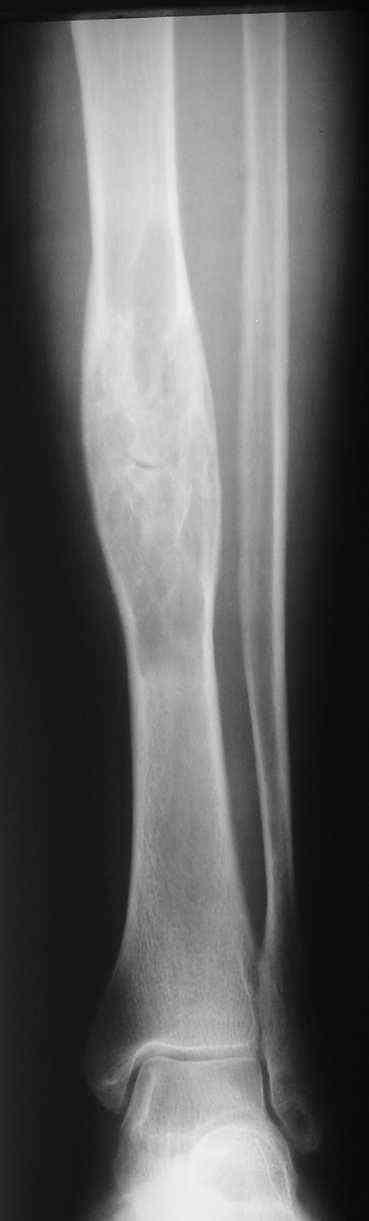

Я поддерживаю мнение доктора Odessky Jacob, что это образоавние возможно фиброзная дисплазия. Случай из моей практики - смотри рентгенснимки во вложении. Правда у моего пациента -полиосальная форма и болезнь проявилась в раннем детстве.

По представленным снимкам наиболее вероятен диагноз "фиброзная дисплазия".